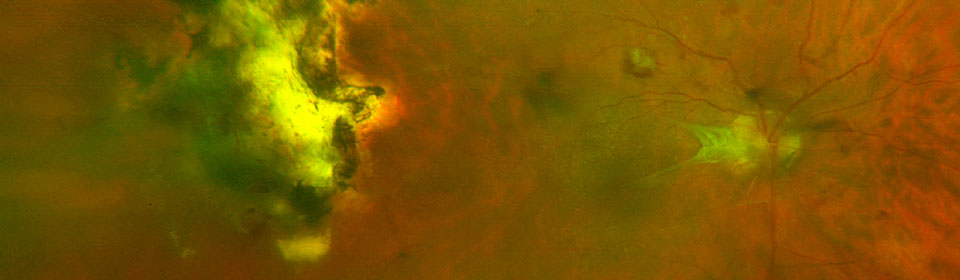

Almost 1 in 10 diabetics has sight threatening retinopathy.

Diabetes is the leading cause of blindness in the 25 to 75 age group.